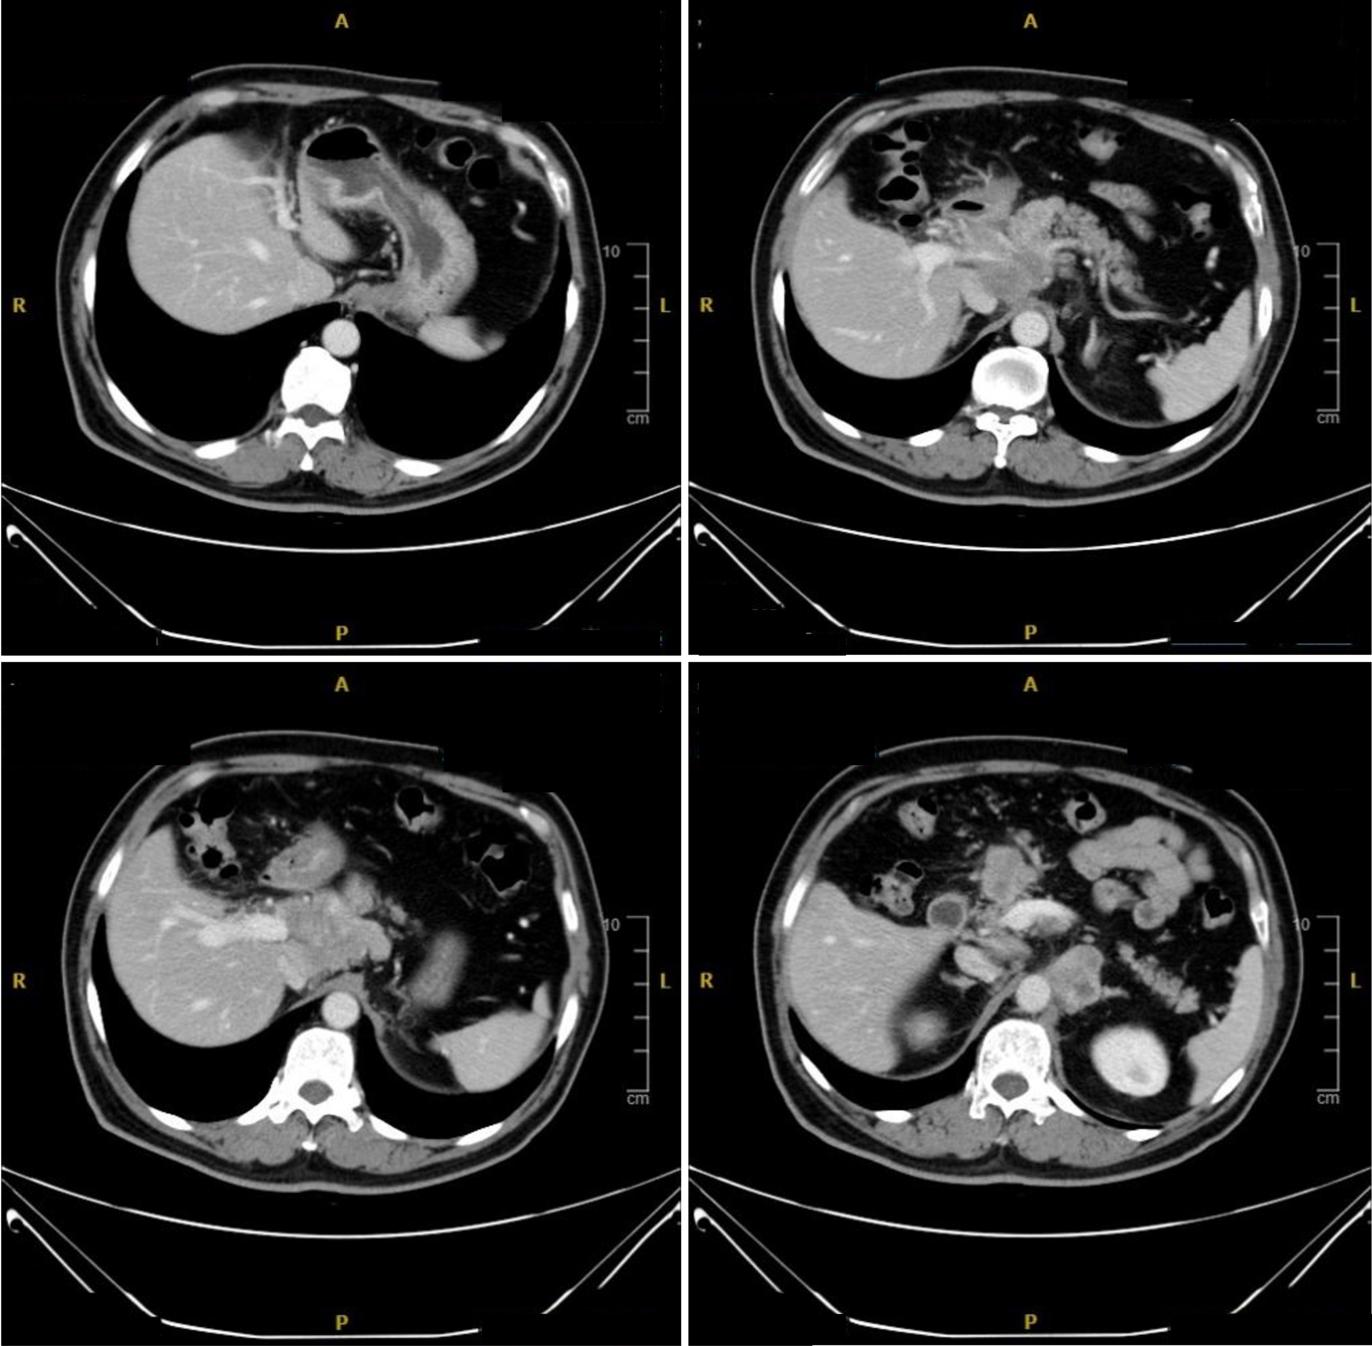

8周期治疗后疗效评估(CT复查:2023年04月06日): 胃窦胃壁稍致密肿胀同前,胰腺颈部病灶较前变化不大;腹腔、腹膜后多发肿大淋巴结,部分较前稍缩小,个别稍增大。

9.png

图5. 治疗6周期后(2023年02月20日)与治疗8周期后(2023年04月06日)CT对比

放射治疗(SBRT)联合免疫治疗:2023年04月18日起予胰腺转移灶及转移淋巴结SBRT治疗,剂量68Gy/17f。放疗后配合舒格利单抗免疫治疗协同增效。

放疗后疗效评估(CT复查:2023年06月27日): 胃窦壁稍显增厚,目前病灶显示不明确,较2022年09月21日首诊片好转;腹腔及腹膜后多发肿大淋巴结,大部分较前变化不大,个别较前缩小,原胰腺颈部病灶目前轮廓显示不明确,局部密度稍显致密。

10.jpg

图6. 治疗8周期后放疗前(2023年04月06日)与放疗后(2023年06月27日)CT对比